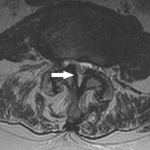

ხერხემლის სტენოზის MRI: ისრებით მითითებულია ხერხემლის არხის საშუალო ფორმის სტენოზი. ის გამოწვეულია ფასეტური სახსრისა და ყვითელი იოგების ჰიპერტროფიით

ექიმ Dr K. Singh საკუთრება; გამოყენებულია ნებართვით